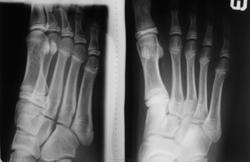

Случай №1 Мальчик 12 лет пришёл на снимок для исключения перелома основания 5 плюсны.

Случай №2 Молодая балерина пришла для исключения перелома 5 плюсны

Хорошо сломали - и ясно видно, и без смещений. Случай 1 - перелом основания V плюсневой кости правой стопы; случай 2 - косой перелом головки V плюсневой кости левой стопы (ещё какие-то кистовидные просветления намечаются в головках плюсневых костей, а может это просто игра теней...)

И в первом, и во втором случае имеется перелом 5 плюсневой кости без смещения (в первом случае - бугристость, втором - дистальный конец).